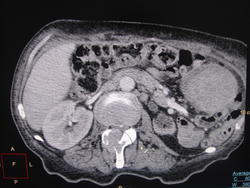

Женщина 5 лет назад прооперирована по поводу рака яичника, посл раз была в ООД 2 месяца назад- написали-опухоль 4 ребра, понятно, что метастаз. Очень тяжелый и интересный случай. Произошел делёж между хирургами и гинекологами, кто должен лечить. Хирурги- первично яичники- не мы. Гинекологи- оперировалать по ним давно- не наша, лечить по последствиям.. СКТ обследование всё расставило на свои места, хирурги сплавили больную по "профилю", в чем убедились в силе европейской техники

Поражение грудной клетки я б описала кратко: множественные остеолитические мтс рёбер, позвонков, с экстраоссальным мягкотканным компонентом от ... до ... см, ... ед.Н плотности. Посмотрите на легочном окне в MIP режиме сами легкие, могут быть и там мтс.

Лимфоузлы мне оценить сложно при таком оттеснении кишечника и немногочисленности аксиалов. Возможно, поражение брыжеечных узлов. но не уверена... Парааортальные, бифуркационные и подвздошные общие лимфоузлы в виде конгломератов до ... см. В малом тазу определяется мягкотканное образование ... ед.Н плотности размерами ...х...х... см. В большом сальнике слева на уровне ... позвонков определяется гигантский мтс размерами...х... см.

С малотазовым образованием непонятно, где оно, кроме того, что между мочевым и прямой кишкой - сориентируйтесь по аксиалам и короналам, что и куда оно оттесняет.

На счёт сальника могу ошибиться... посмотрите, где по отношению к этой блямбе расположена ободочная кишка, по аксиалам, сагитталам - если толстая кишка кзади от мтс, то точно мтс в сальнике.

А что с левой почкой?

Гипотрофия, если левая почечная артерия нормального калибра; гипоплазия, если артерия мелкая, узкая. Поправки к определению с удовольствием почитаю